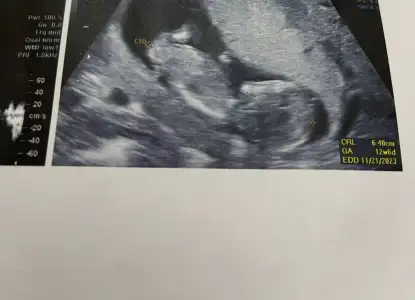

Ayy bende senin gibiyim aynı canım 13+3teyiz şuan aklım hep bebekte. Bir hareketlerini hissedebilseydikHaha mantıklı evet. Ama üç gündür iyi hissetmediğim için bebeği de merak ediyorumiçgüdüsel işte

Ayy bende senin gibiyim aynı canım 13+3teyiz şuan aklım hep bebekte. Bir hareketlerini hissedebilseydikHaha mantıklı evet. Ama üç gündür iyi hissetmediğim için bebeği de merak ediyorumiçgüdüsel işte